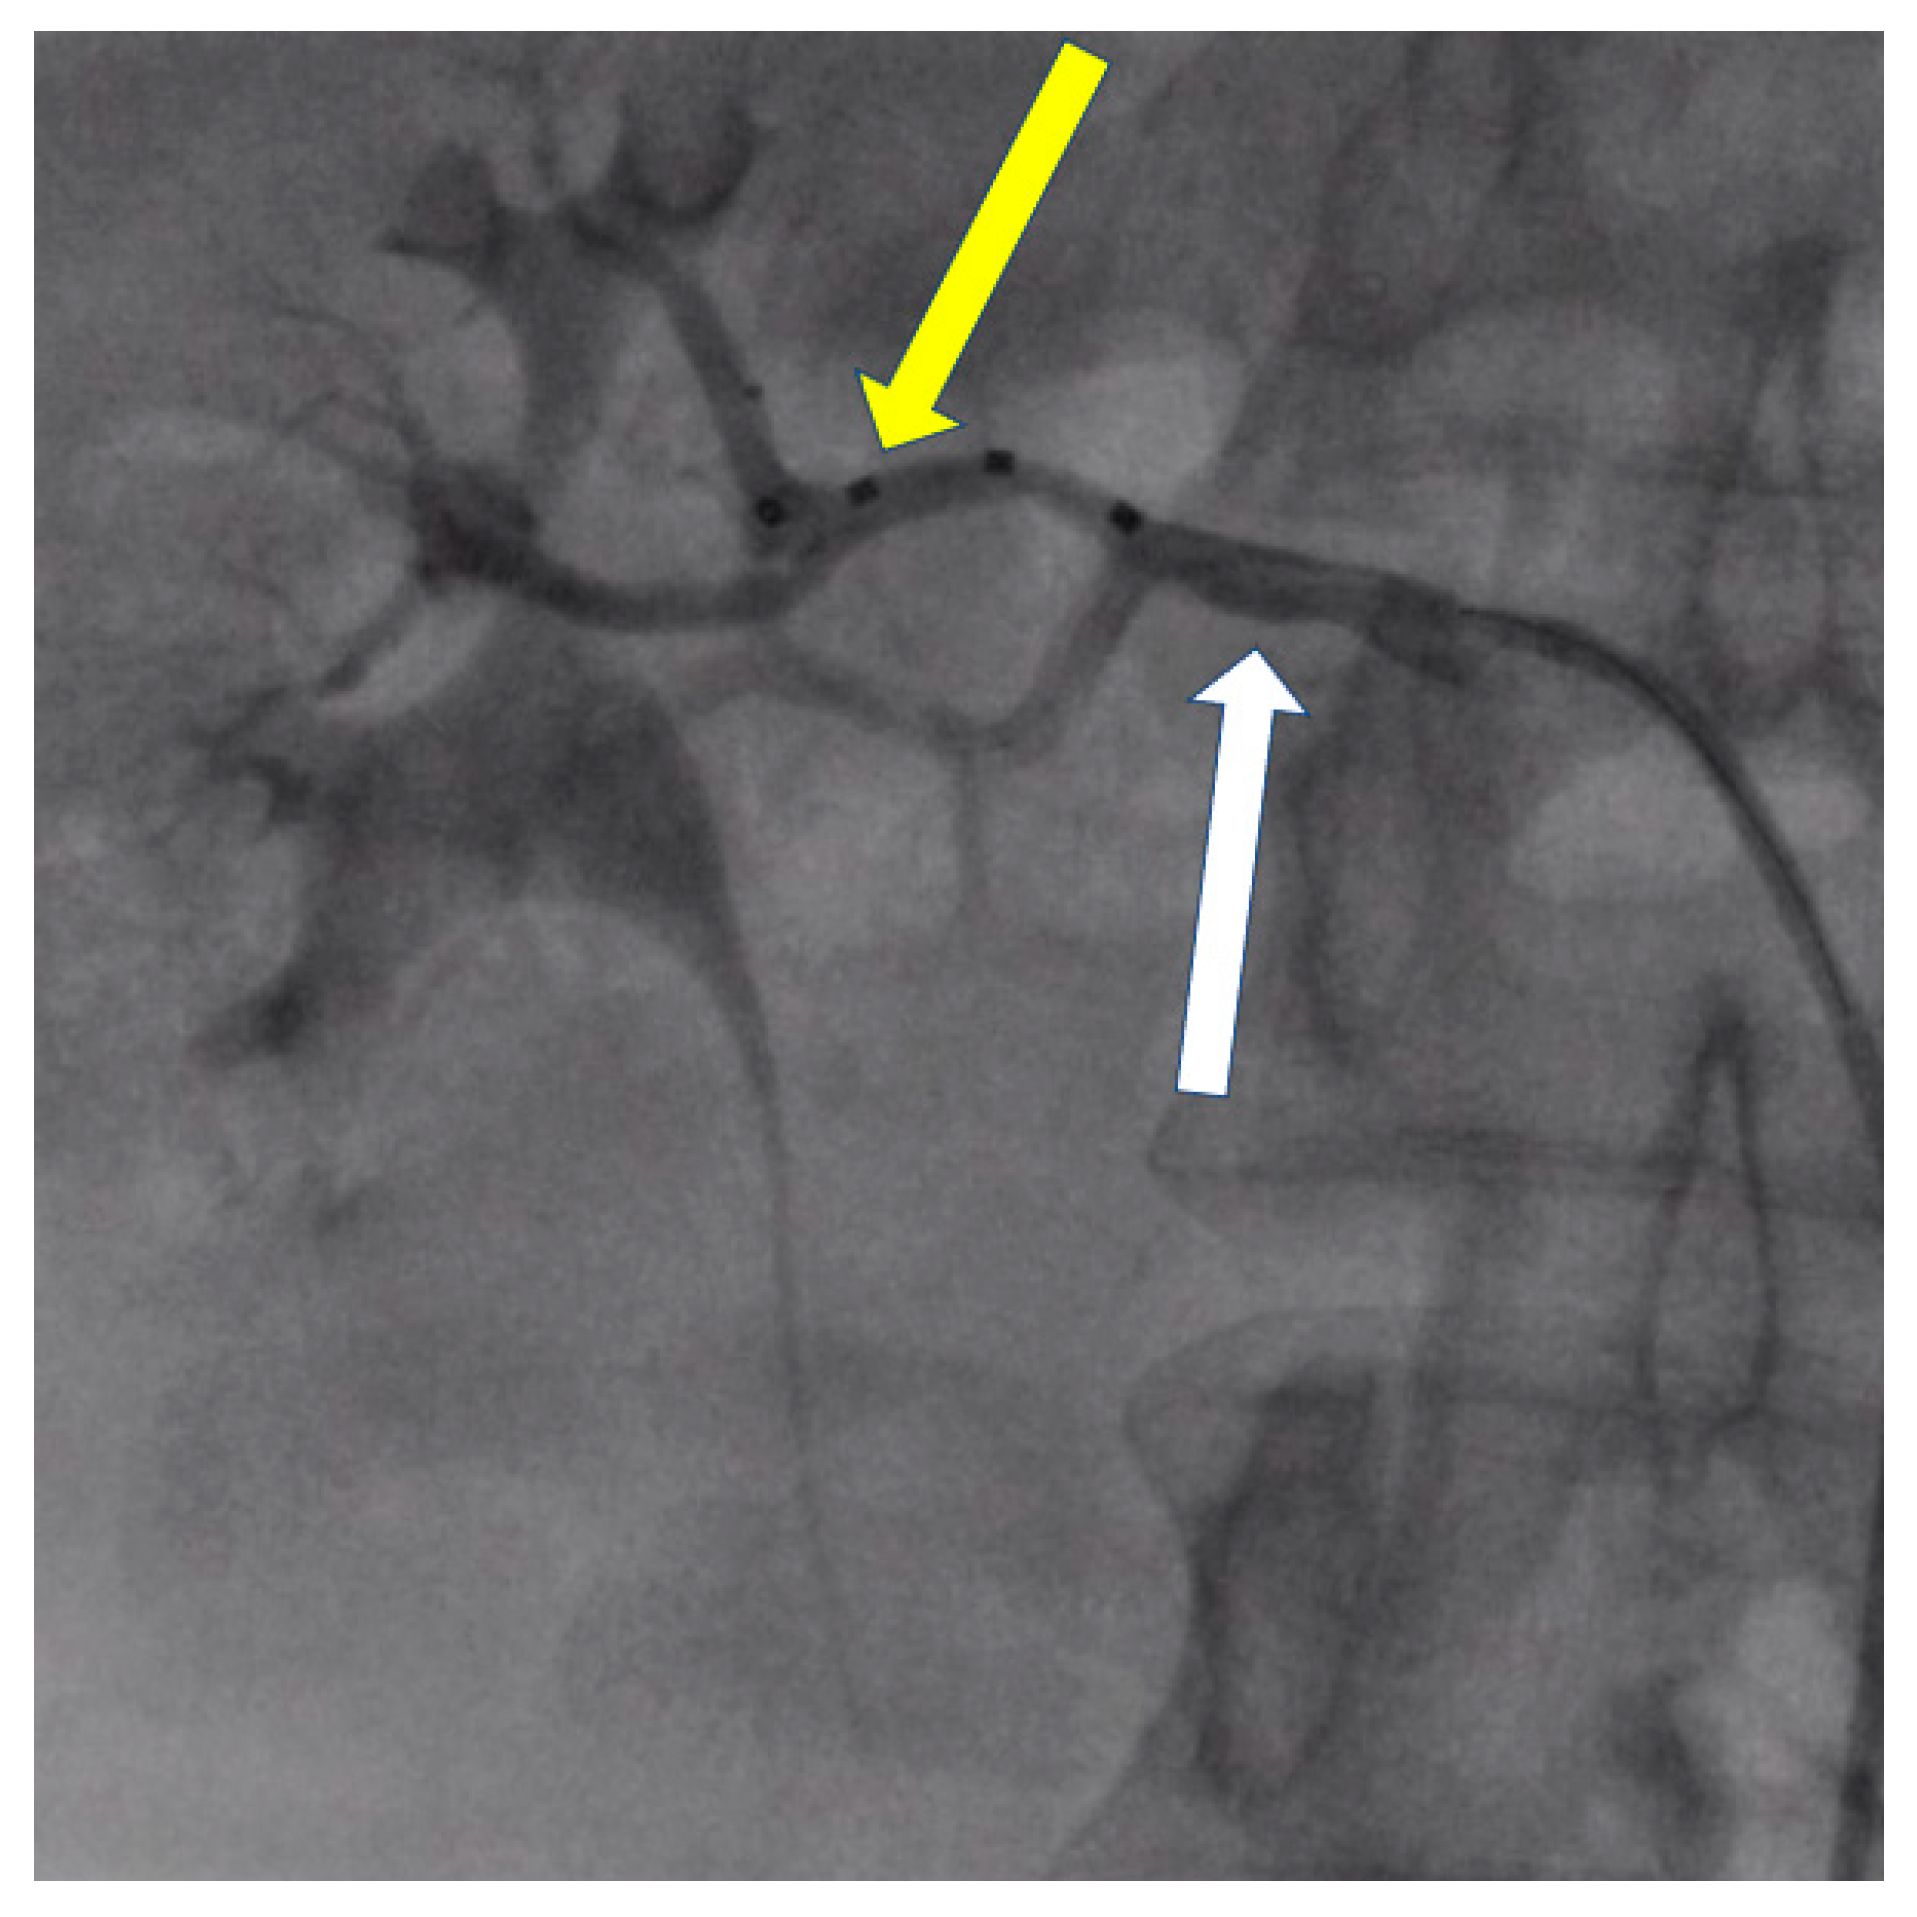

- Tokarek, T.; Rajtar-Salwa, R.; Rzeszutko, Ł.; Bartuś, S. Long-term benefit of redo sympathetic renal denervation in a patient with resistant hypertension. Postep. Kardiol. Inter. 2021, 17, 239–241. [Google Scholar] [CrossRef] [PubMed]

- Atas, H.; Durmus, E.; Sunbul, M.; Mutlu, B. Successful accessory renal artery denervation in a patient with resistant hypertension. Heart Views 2014, 15, 19–21. [Google Scholar] [PubMed]

| de Leon-Martinez, Enrique Ponce et al. [45] | 55-yo man | Proximal bifurcation in the left RA and right ARA | RDN, RF ablation catheter (Symplicity Medtronic) | Five to two drugs | −29/9 after one month, −50/20 after two moths |